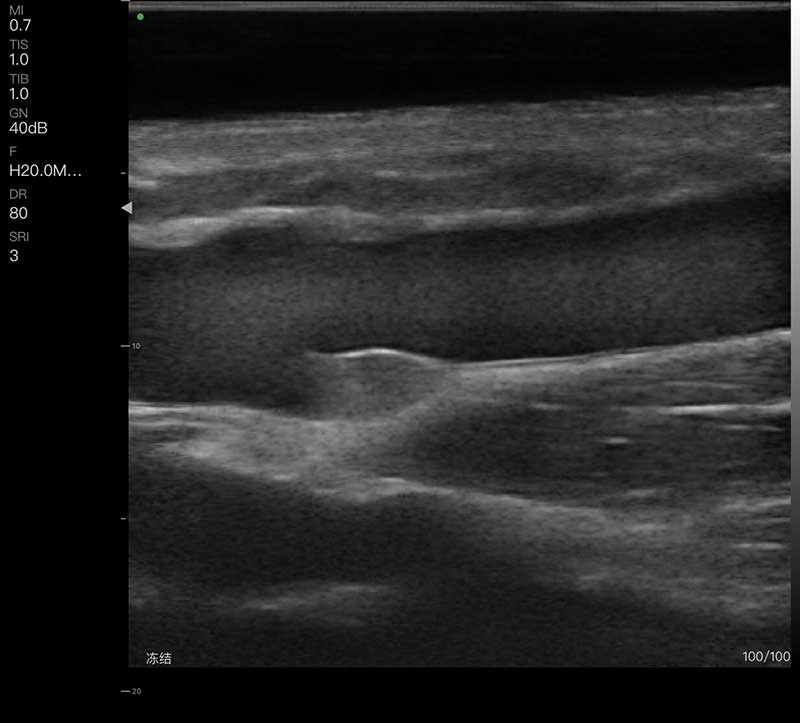

• 扫描方式:电子阵列扫描

• 探头频率:18/22MHz

• 阵元数:192

• 通道数:64

• 扫描宽度:15mm

• 扫描深度:10/15/20/25mm,可调

• 显示模式:B、B/M、COLOR、PDI、PW